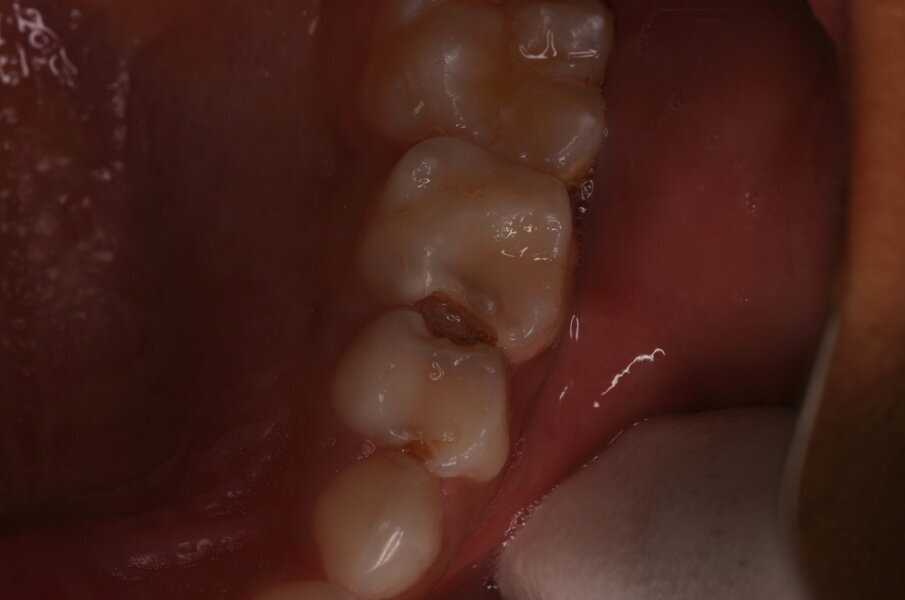

Afbeelding 5a. Onvoldoende toegankelijke caviteit mesiaal in de 65, distaal in de 64 en mesiaal in de 64.

Afbeelding 5b. De gedemineraliseerde caviteitsranden zijn onondersteund en fractureren gemakkelijk door met een glazuurmes erop te drukken.

Afbeelding 5c. De kleine mesiale caviteit in de 64 is door middel van de ART-methode gerestaureerd. De andere twee caviteiten zijn nu toegankelijk voor tandenborstel en fluoridetandpasta.